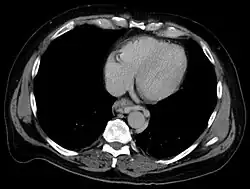

Esophageal varices are extremely dilated sub-mucosal veins in the lower third of the esophagus.[1] They are most often a consequence of portal hypertension,[2] commonly due to cirrhosis.[3] People with esophageal varices have a strong tendency to develop severe bleeding which left untreated can be fatal. Esophageal varices are typically diagnosed through an esophagogastroduodenoscopy.[4]

Dilated submucosal veins are the most prominent histologic feature of esophageal varices. The expansion of the submucosa leads to elevation of the mucosa above the surrounding tissue, which is apparent during endoscopy and is a key diagnostic feature. Evidence of recent variceal hemorrhage includes necrosis and ulceration of the mucosa. Evidence of past variceal hemorrhage includes inflammation and venous thrombosis.